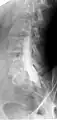

![]() Myelogram showing arachnoiditis in the lumbar spine. | |

Conventional myelography in oblique projection. You can see the individual nerve root sheaths.